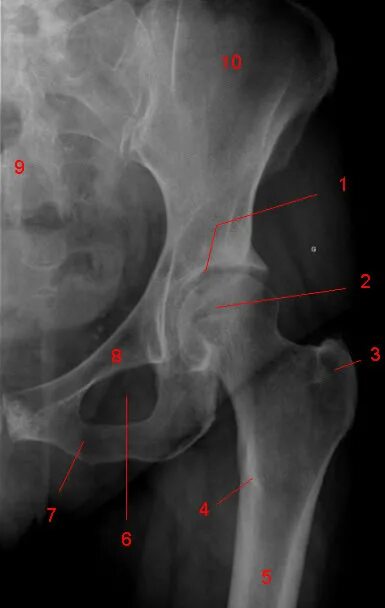

Рентген тазобедренный в двух проекциях